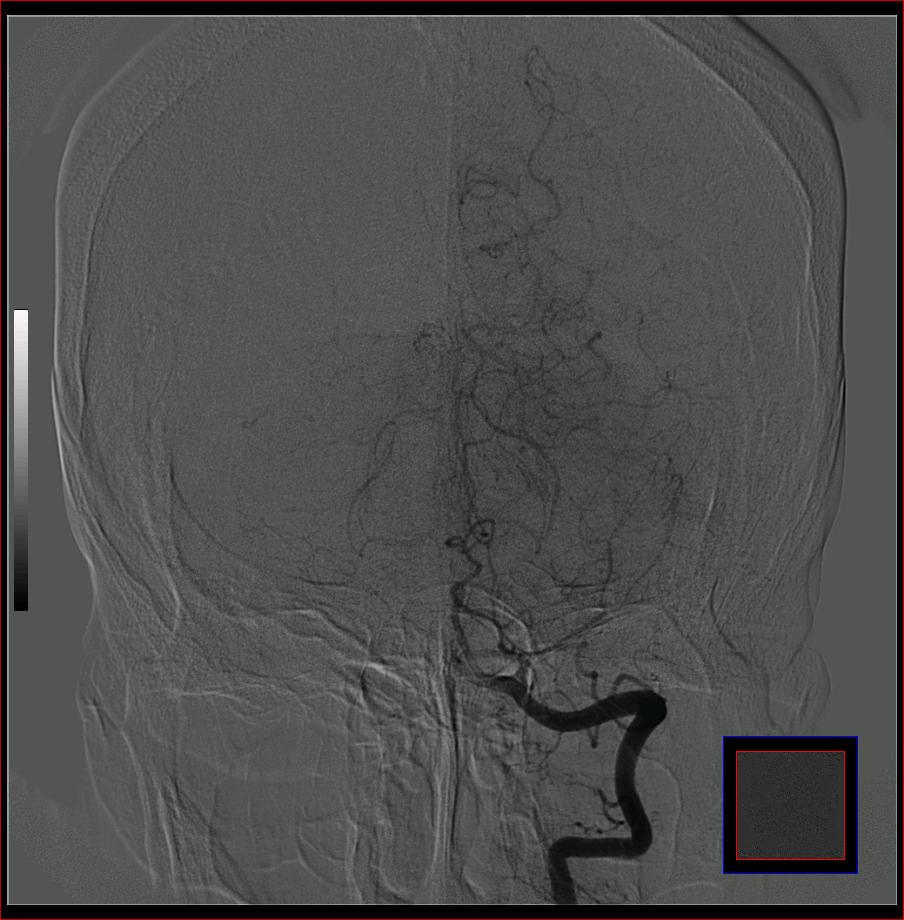

标题: DSA0121:脑血管造影

男,65岁,肢体无力。

大脑前动脉a2段动脉瘤.

右侧大脑前a缺如.左侧大脑中动脉m1段狭窄,远端分支分布稀疏.

前交通或稍远端动脉瘤要仔细查,左大脑中动脉狭窄要鉴别,有可能是痉挛,因为造影导管插得稍深啦。其它就是供血动脉变异较大

烟雾病